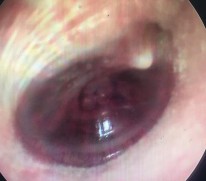

Hình ảnh nội soi tai

Ảnh 12 MN dính vào ụ nhô, khớp đe đạp MSBA. 1901263977 |